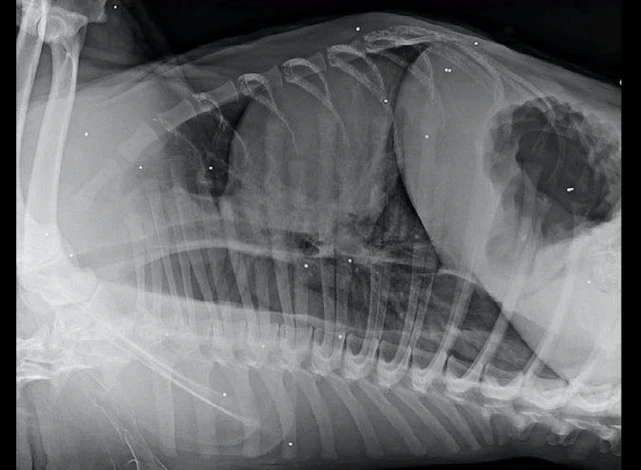

而经过医生的一番检查之后,才知道脸肿的原因。罪魁祸首就是它脖子上的一根鞋带,不知道是谁死死系上了死扣。很明显这并不是牵引绳,而是有人故意而为之,想要将它置于死地啊!除此之外,在给狗狗拍片后,发现它的体内还有子弹碎片!它之前到底是经历了什么,又是被系绳又是被当靶子。唯一值得庆幸的是,狗狗逃掉了所有的噩运还活着,现在被救助,就还有生活下去的希望!

很快医院便给狗狗安排了手术,术后它肿胀的脸终于是憋下去了。不过由于脖子长时间被憋着血流不通,下巴的皮肤有明显的松弛,看起来还是有点奇怪,不过只要是经过慢慢的治疗,它肯定会成为一只正常的狗子的!而还有一个好消息,有一对年轻的夫妻听说狗狗的遭遇后,就申请领养了它,狗狗将会在它的新家中继续康复了。也许是之前的经历太痛苦,狗狗被救助后还总是一副哭丧着脸,希望它能尽快忘却以前的伤痛吧!